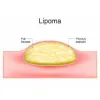

Lipoma Surgery